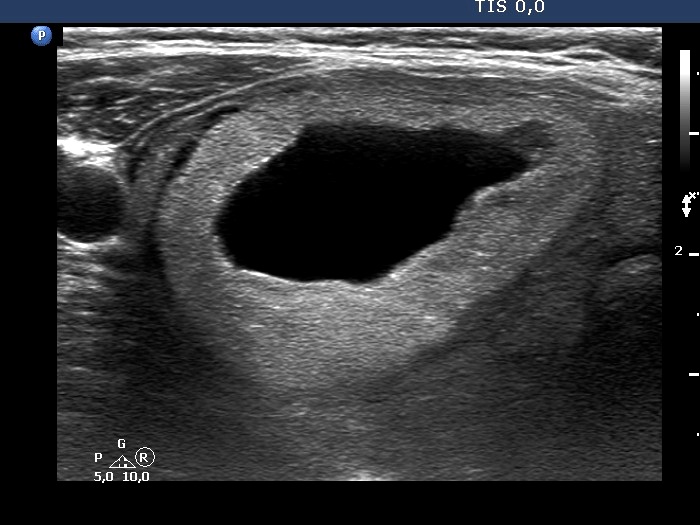

First examination (first row of images):

Clinical presentation: A 68-year-old woman was referred for evaluation of a nodular goiter discovered on routine physical examination.

Palpation: Both lobes had elastic nodule.

Results of blood test: TSH 4.21 mIU/L, FT4 11.9 pM/L, aTPO 481 U/mL.

Ultrasonography. The thyroid was moderately hypoechogenic. There were two central-type cysts, one in the left lobe and another one in the right lobe. Both had perinodular vascularization.4 mL serous fluid was aspirated. Aspiration cytology resulted in benign cystic lesion.

Suggestion: yearly TSH-determination, ultrasound in three years.